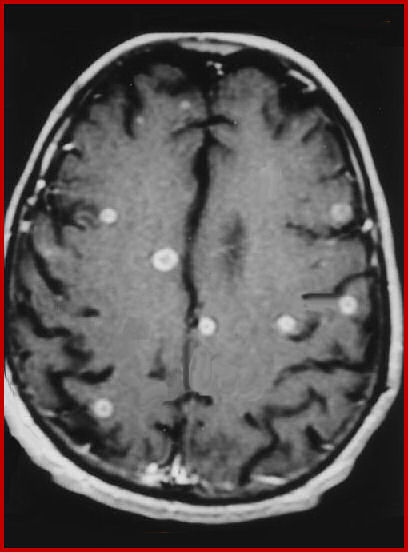

Cerebral lesions Of multiple Sclerosis: Is Gadolinium Always ...

Gadolinium for assessment of multiple sclerosis lesion activity • 179 only ring-enhancing lesions seemed to be associated with a worse prognosis. ... Access This Document

MRI Distinguishes Brain Lesions - Catersource

MRI distinguishes brain lesions, possibly supplementing existing diagnostic algorithms MR images can reveal perivenous multiple sclerosis (MS) lesions, and distinguish them from microangiopathic lesions, according to a study published in the Multiple Sclerosis Journal. ... Retrieve Document